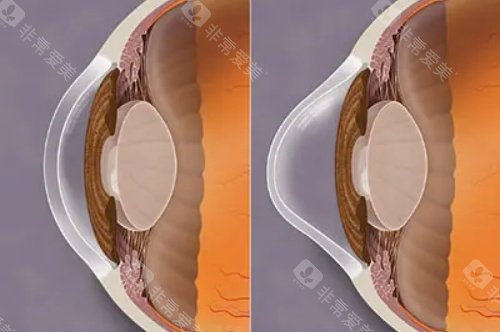

术中:使用龙晶PR人工晶体(国产初款睫状沟固定型晶体)增强角膜稳定性